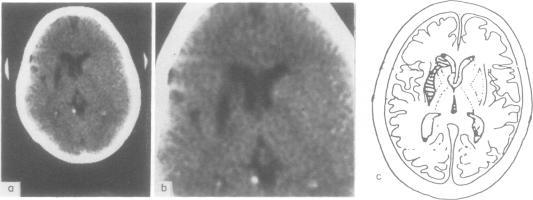

Three cases of unilateral dystonia of vascular origin are presented and compared with those in the literature. Damage in the region of the lenticulostriate arteries accounted for ischaemic lesions of the putamino-capsulo-caudate region, the external pallidum probably also being involved. This syndrome appears if the ischaemic accident took place during childhood. The functions of each of these structures and the possible role of the anterior limb of the internal capsule are discussed.

本文报告了3例血管源性单侧肌张力障碍病例,并与文献中的病例进行了比较。豆纹动脉区域的损伤导致壳核-内囊-尾状核区域的缺血性病变,外苍白球可能也受累。如果缺血性意外发生在儿童期,则会出现该综合征。文中讨论了这些结构各自的功能以及内囊前肢可能发挥的作用。